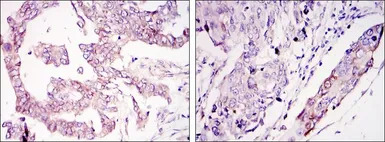

IHC-P analysis of ovary tumour tissue (left) and lung cancer (right) using GTX82765 WIF1 antibody [1G5].